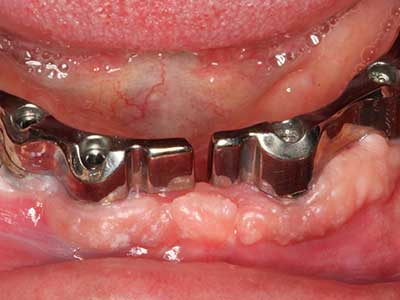

Für die Entnahme von Implantaten ist die Präparation eines vestibulären Knochendeckels möglich, der nach Entfernung der Implantatschraube refixiert wird und auf diesem Wege die Kontur des Alveolarfortsatzes erhält.